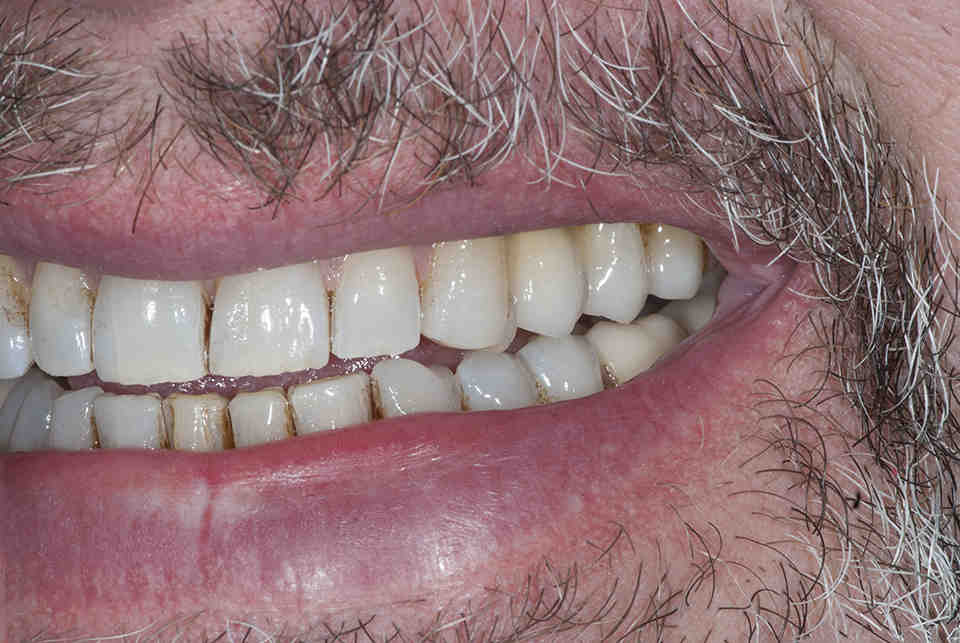

From www.facialart.com

Removal of a Dental Implant with Advanced Bone Loss Followed by Bone What Causes Bone Loss After Dental Implants Damage to the tooth can be caused by various etiological factors like periodontal disease, abscess formation, trauma, or vertical. A bone grafting procedure increases the amount of bone in an area of the jaw where there is bone loss or where there is a need for additional support. It develops due to chronic inflammation at the site of the implant.. What Causes Bone Loss After Dental Implants.